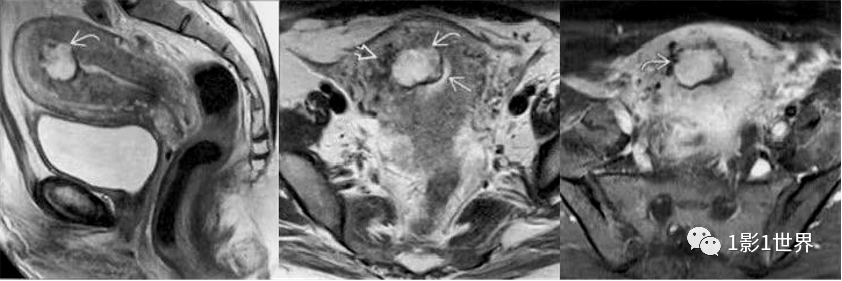

侵袭性葡萄胎,极少数绒毛变性可侵入到肌层,甚至发生远处转移。从组织学上看,属于水泡状胎块,不属于肿瘤。

影像诊断

MRI检查

宫腔内多发T1WI低信号、T2WI高信号、DWI低信号的小囊样病变,有纤细分隔,呈蜂窝状或葡萄状,病变包膜完整。

子宫肌层受压变薄,结合带完整

增强扫描:表现为在扩张的子宫内膜腔内含有多个小囊腔样强化的异质组织,动脉期轻度不均匀强化,静脉期及延迟期渐进性网格状强化;宫旁见多发迂曲流空信号影,增强后可呈血管样强化